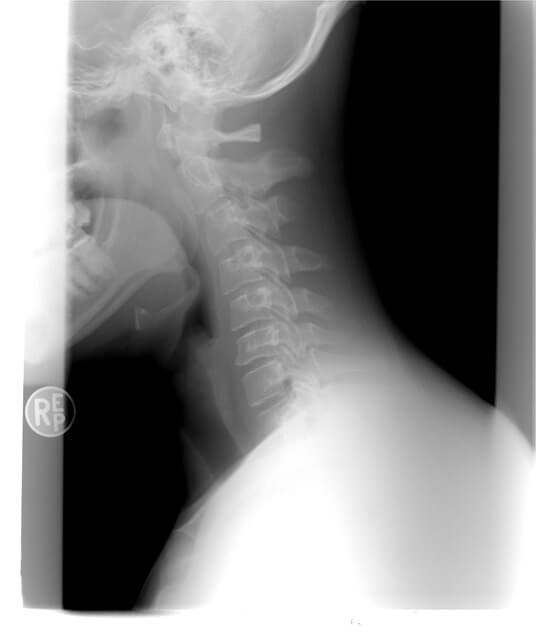

정상적인 목은 알파벳 C 형태로 커브를 이루고 있는데, 현대인들의 잘못된 습관으로 인하여 유연성이 사라지고 일자 형태의 경직된 목 상태를 '일자목'이라고 합니다. 일자목은 정상적인 형태와는 달리 신경이 눌리고 근육이 경직되기 때문에 목디스크까지 유발하고, 만성 두통을 만들기도 합니다.

정상적인 목의 형태는 C자를 꾸준히 유지하는데, 점차 일자목과 거북목이 되면서 머리가 어깨 앞으로 나가는 모양을 지속되는데, 옆에서 봤을 때 더 확실하게 관찰되고 있습니다.